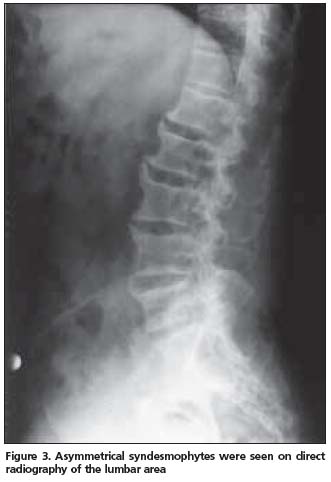

Anterior longitudinal ligament calcification, fusion of multiple facet joints and atypical syndesmophytes were found on cervical spine X-rays (Figure 1) and coarse, asymmetrical syndesmophytes were seen on thoracic (Figure 2) and lumbar spine (Figure 3) X-rays. No abnormalities suggesting PsA or gout were seen on hand and foot radiographs. The magnetic resonance imaging (MRI) of the sacroiliac joint and computerized tomography (CT) of atlanto-axial joint were normal.